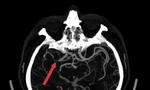

Vết thương rộng khoảng 6cm, gây phù nề biến dạng cổ bên trái, tổn thương tuyến giáp, chèn ép khí quản gây suy hô hấp cấp. Động mạch cảnh bị đứt khiến não tổn thương não nặng vì thiếu máu nuôi. Đồng tử người bệnh đã co nhỏ, phản xạ ánh sáng chậm, hôn mê sâu. Các bác sĩ tiên lượng người bệnh tử vong.

“Sau 4 giờ 30 phút khẩn trương trong phòng mổ, ê kíp đã khâu phục hồi được động mạch cảnh, kiểm soát tái tưới máu, khâu phục hồi tuyến giáp, lấy máu tụ, đặt dẫn lưu và thực hiện các biện pháp ngăn chặn nguy cơ hình thành máu đông di chuyển lên não bệnh nhân. 9 ngày sau phẫu thuật, bệnh nhân đã qua được nguy kịch, tri giác và vận động đã phục hồi gần như bình thường” – BS.Nhân nói.